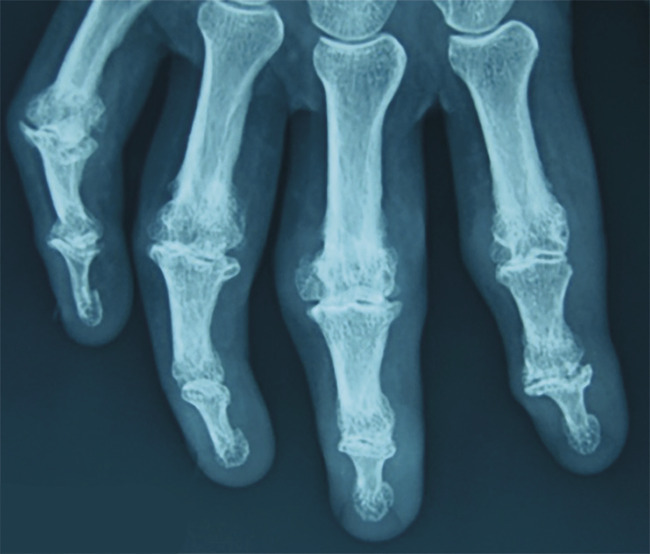

L’arthrose est très courante et peut atteindre quasiment toutes les articulations. Deuxième localisation de la maladie, les lésions digitales peuvent être trompeuses lors des poussées. Les déformations caractéristiques des interphalangiennes distales (IPD) [nodosités d’Heberden] ou moins fréquemment des interphalangiennes proximales (IPP)[Bouchard] sont d’apparition lente et bien mises en évidence sur une simple radiographie (fig. 2 ).